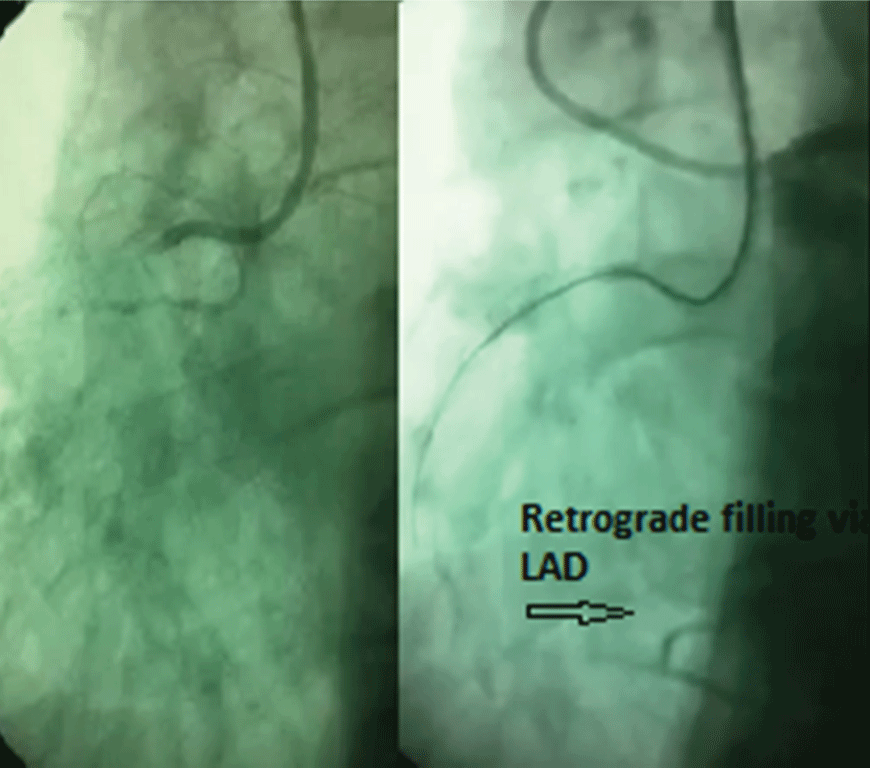

Since the patient did not have any symptoms and there weren't any signs of perforation in the angiography, we decided to leave this guidewire subintimally and went on the procedure with another conquest pro guidewire. We were able to cross the lesion with the second guidewire and recanalized the occluded segment by stent implantation. The entrapped guidewire was in the subintimal space and fully covered with the stent (Figure 3). The patient was discharged on the second day following the intervention without any symptoms after performing transthoracic echocardiography which confirmed that there was no new regional wall motion abnormality and pericardial effusion. Follow-up visit at the sixth month indicated a symptom free interval without any ischemic type chest pain.

Figure 3: Full coverage of the dissection and the fractured guidewire after stent implantation into the chronic occluded segment.